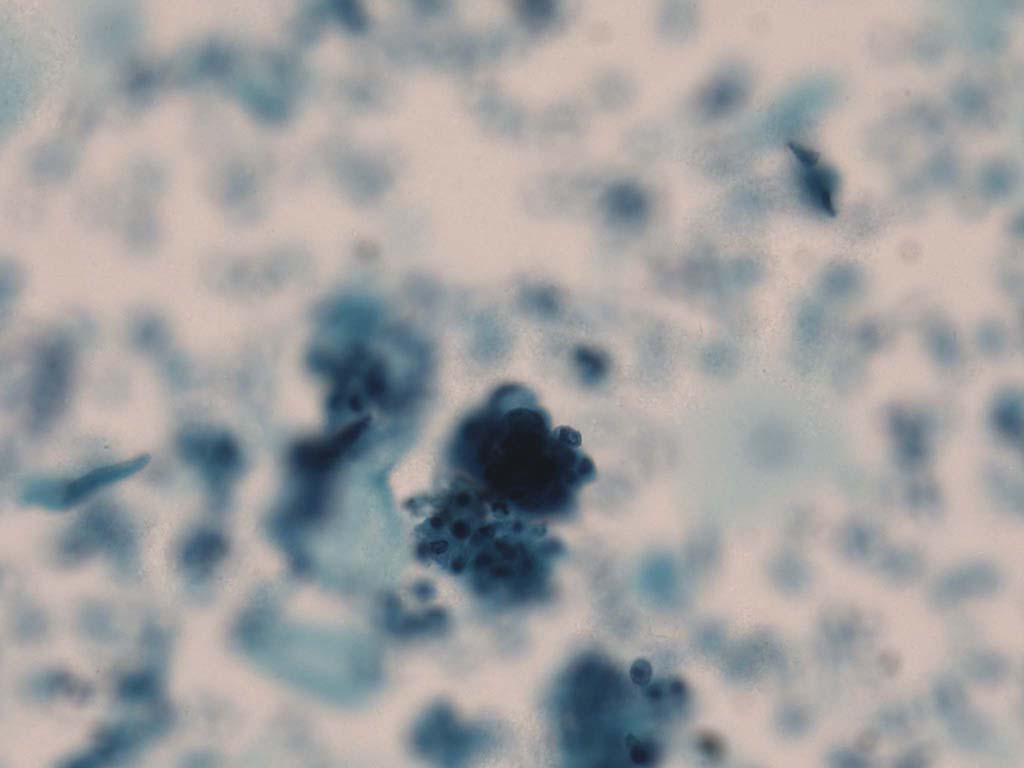

A good image fusion method should contain the following properties. First, it preserves both the details of small size objects and the integrity information of large size objects in the fused image, even in the case of the size of the interested objects varying largely in the image. For example, the cervical cell images from the microscope contain both small size isolated cells and large size agglomerates, which are both useful for cervical cytology [5]. Second, it should be efficient enough to handle large-scale data. For instance, it needs to process thousands of fields of view (FoV) in an acceptable time for the whole slide scanning in digital cytopathology [6], which requires to fuse a series of high resolution images captured at each FoV in a very efficient way. Third, it does not produce obvious artifacts. Despite being studied extensively, to our best knowledge, existing fusion methods may not meet these requirements simultaneously.

To demonstrate the effectiveness and efficiency of the proposed image fusion method , we conduct a set of comparative experiments on three image datasets. The first is composed by 8 pairs of multi-modal medical images and the second one contains 15 pairs of multi-focus gray or color natural images. These two datasets are often used in many related papers and some examples are shown in Figure 3(a) and Figure 3(b). The third one is a new multi-focus cervical cell image dataset collected by ourselves, which consists of 15 groups of color images and each group contains a series of multi-focus cervix cell images with size of or , etc. Some source examples are shown in Figure 3(c). Our source code implemented in C++ along with the new multi-focus cervical cell image dataset is available online.

Figure 9, Figure 10 and Figure 11 show the comparative fused results of the multi-focus cell images shown in Figure 3(c). For clarity, we also present a closeup view in the right-bottom of each sub-picture in Figure 9 and Figure 10. As shown in the close-up views of Figure 9, the fused images based on DSIFT, IM, MWGF and BF methods are extremely blurred in the boundary and fail to keep the details of cell nucleus. Furthermore, the DTCWT and NSCT based methods produce halo artifacts in the fused images, while GFF and CNN based methods fail to preserve the small cell nucleus. LP-SR based method nearly works fine which keeps the most of the details of the small size cells, but the integrity of the clustered large size cells is damaged. Fortunately, in our proposed method, the integrity of the clustered large size cells is preserved and most of the isolated small size cells are maintained from the original images, which demonstrates the best visual quality.

Similarly, as shown in the close-up views of Figure 10, the fused images from DSIFT, IM, MWGF and BF are blurred and lose some nucleus details, while the results from DTCWT, GFF, CNN and NSCT produce halo artifacts. LP-SR based method can keep details well but also produces halo artifacts and other noise. Our method can preserve the focused areas of different source images well without introducing any artifacts. For the example illustrated in Figure 11, the fused images generated by DSIFT, DTCWT, IM and NSCT all fail to preserve the focused areas of different source images and result in extremely blurred images. The GFF, CNN, MWGF and BF based method introduces a lot of color distortion of the nucleus regions and the obvious halo artifact. The result of LP-SR based method is close to the one of our method but introduces some odd color distortion. Again, our method produces fused image which can preserve the focused areas of different source images well without introducing any artifacts.